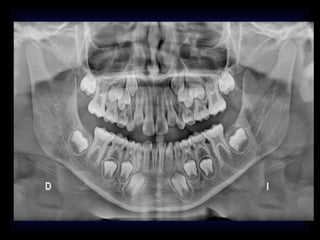

RADIOGRAFIAS MAS COMUNES

EN DX ODONTOLOGIA

RADIOGRAFIAS DX ODONTOLOGICO

• ANTERO POSTERIOR

• A.P DE TOWNE

• A.P. DE WATERS

• PROYECCIONES LATERALES

• PROYECCION A. DE CADWELL

• PANORAMICA

• PERIAPICAL

• R.BITE WING

FIN

RADIOGRAFIAS DX ODONTOLOGICO •ANTERO POSTERIOR • A.P DE TOWNE • A.P. DE WATERS • PROYECCIONES LATERALES • PROYECCION A. DE CADWELL • PANORAMICA • PERIAPICAL • R.BITE WING